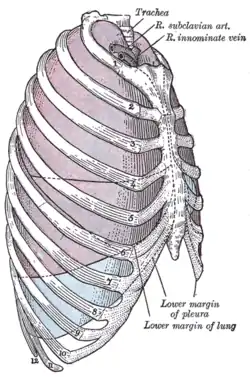

In DVT in the arm, the first (topmost) rib can be surgically removed as part of the typical treatment when the DVT is due to thoracic outlet syndrome or Paget–Schroetter syndrome. This treatment involves initial anticoagulation followed by thrombolysis of the subclavian vein and staged first rib resection to relieve the thoracic outlet compression and prevent recurrent DVT.[146]

The first rib, which is removed in a first rib resection surgery, is labeled 1 in this image